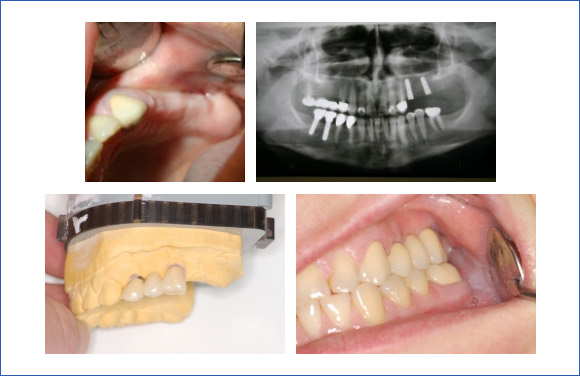

In einer medizinischen und röntgenologischen Untersuchung wird festgestellt, ob die Voraussetzungen für eine erfolgreiche Zahnimplantation bereits gegeben sind oder erst noch erfüllt werden müssen. Ein Abklingen von Entzündungen, eine Ausheilung von Wunden nach Zahnentfernungen oder ein Knochenaufbau gehören manchmal zu den Vorbehandlungsmaßnahmen. Sind diese abgeschlossen, kann das Implantat eingebracht werden.

Im Vorfeld einer Implantation wird Ihre individuelle Mundsituation beurteilt. Es findet eine präimplantologische Untersuchung und Diagnostik mittels Röntgenbildern oder einer digitalen Volumen- tomographieaufnahme statt.

Klinische Beispiele zur Implantatversorgung:

Einzelzahnersatz:

Eine Brückenversorgung kann oftmals vermieden werden. Der Vorteil ist, dass gesunde Nachbarzähne nicht beschliffen werden müssen.

Bei der Versorgung von großen Schaltlücken dient die Pfeilervermehrung zur Stabilisierung des Restgebisses.

Der erste Schritt ist ein genauer zahnärztlicher Befund und ein Röntgenbild. Ebenso werden zur Planung Modelle aus Gips angefertigt ebenso wie Farbfotos der Ausgangssituation.